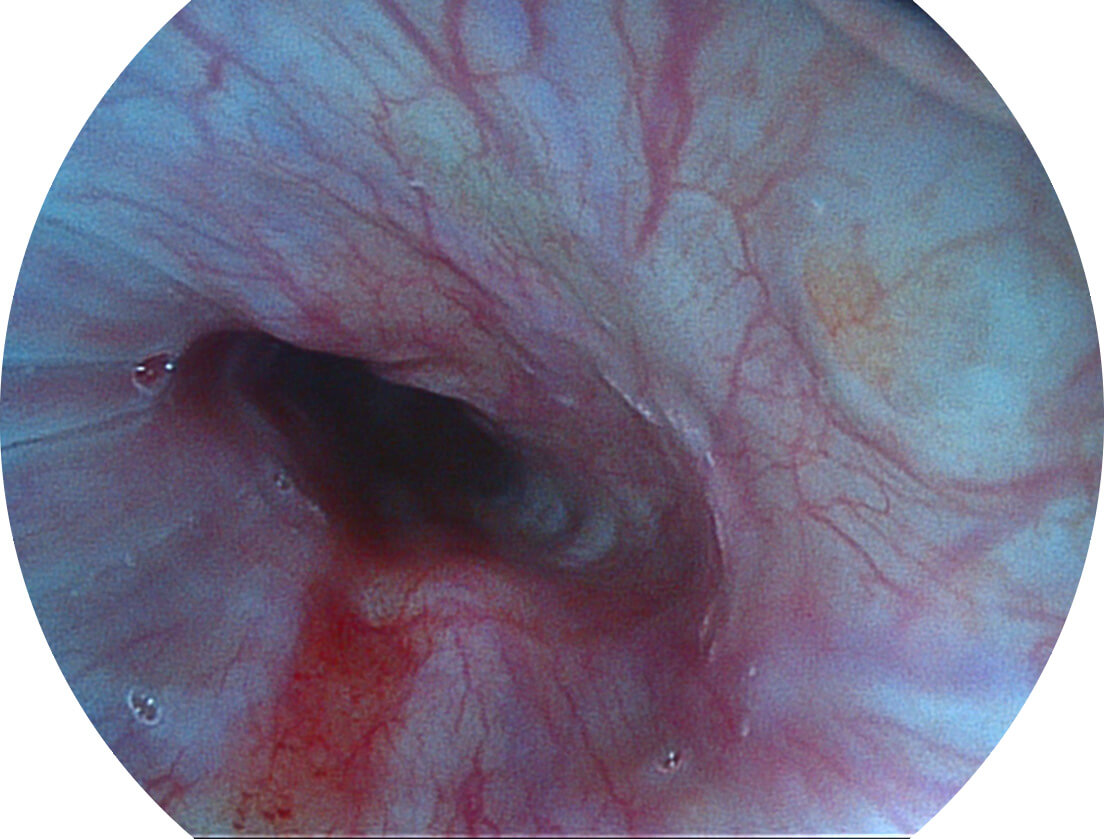

强调浅层黏膜结构的同时,保证照明亮度和提升浅层微血管与中层血管颜色对比度,病变边界更清晰。

• 白光图像 VIST图像